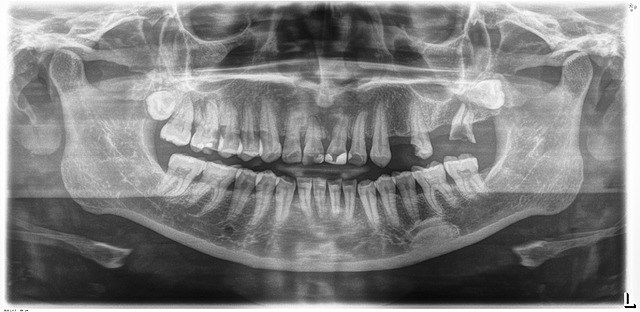

Se realizó la toma de modelos de estudio con material que permite obtener una copia fiel de los tejidos orales del paciente y la radiografía donde se observan las áreas edentulas, los restos radiculares y los terceros molares retenidos

Periodontitis estadio ll, grado B con pérdida ósea horizontal y enfermedad periodontal activa generalizada

caries en OD 1.2, 1.3, 1.5, 1.7, 2.3, 3.6, 3.7, 4.6 y 4.7 Resina filtrada 1.1, 1.6, 2.1

Terceros molares superiores retenidos

Necrosis pulpa y periodontitis apical crónica 1.1

Edentulismo parcial por ausencia de los OD 2.4, 2.6 Y 2.7